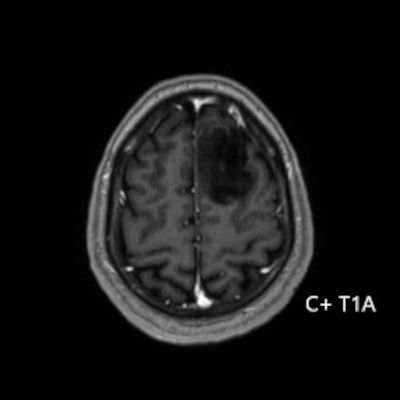

- Sol frontal kortikal-subkortikal yerleşimli aksiyel T2A görüntüde hiperintens sinyal özelliği gösteren (oklar) ve FLAIR görüntüde sinyali ağırlıklı olarak baskılanan (oklar) kitlesel lezyon izleniyor. Lezyon T1A görüntüde hipointens olup post-kontrast T1A görüntüde bu düzeyde patolojik kontrastlanma izlenmiyor (oklar).

- Grade 2 ve 3 tümörlerde çoğunlukla kontrast tutulumu yoktur veya minimal düzeydedir. Grade 4 IDH-mutant astrositomlarda, nekroz veya mikrovasküler proliferasyon varsa heterojen kontrast tutulum gözlenebilir. Kontrast tutulumu her zaman malignite derecesini yansıtmayabilir; bu nedenle biyopsi ve moleküler analiz mutlaka gereklidir.

- Olgumuzda T2-FLAIR mismatch bulgusu mevcut olup, opere edilmiş ve tanısı histopatolojik olarak konulmuştur.